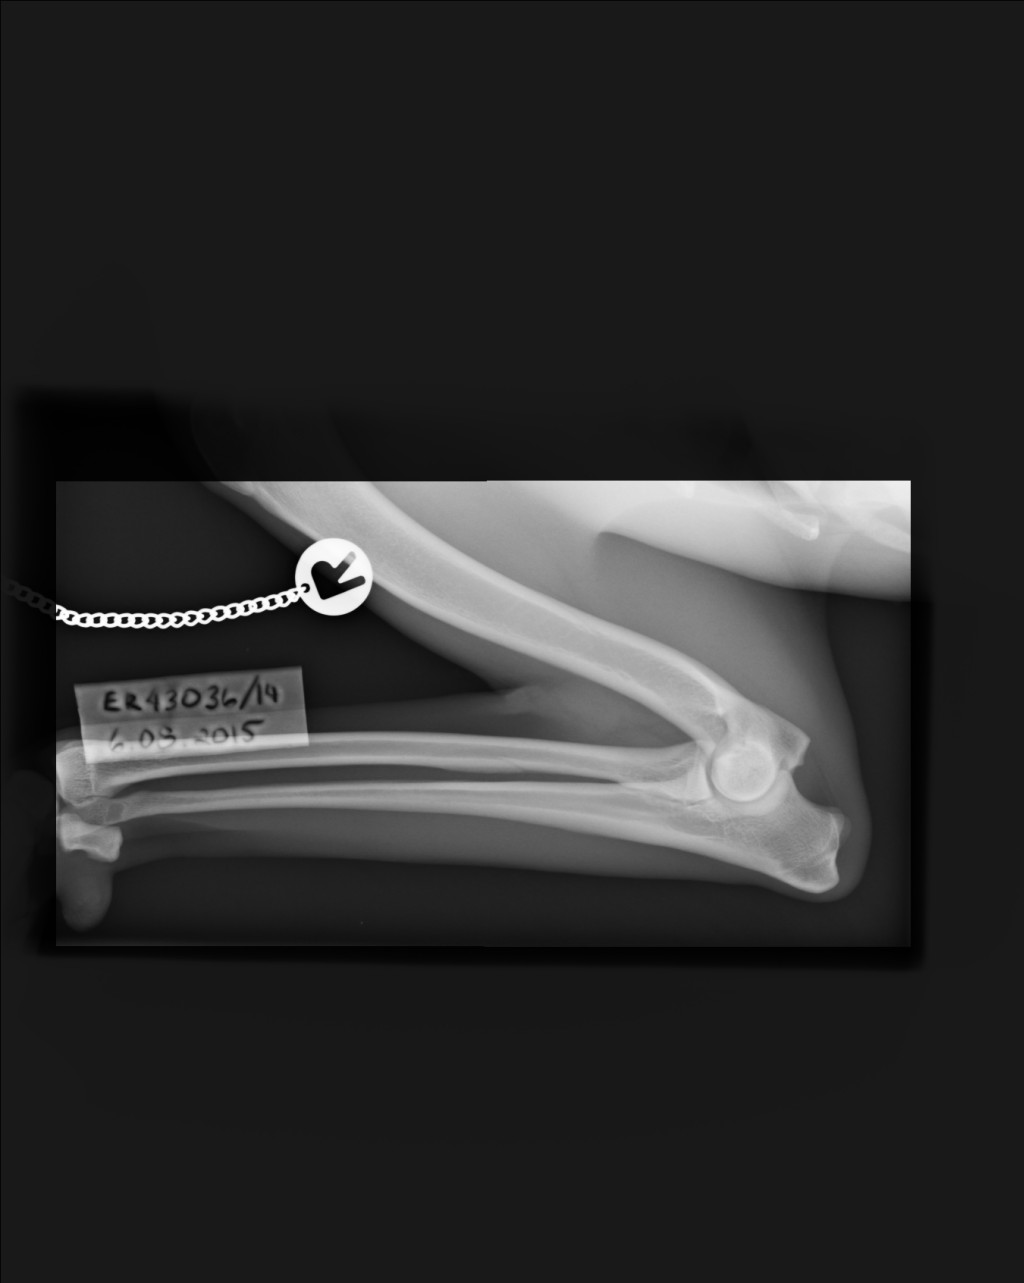

Kennelliitolta nopeaa toimintaa. Kaislan lonkat A/A, kyynärät 0/0 ja selkä terve (VA0 ja LTV0). Alle kaksi -vuotiaaltahan ei saa lausuntoa spondyloosista. Mutta niin ihanaa ja helpottavaa, että Kaisla on terve! Olen niin onnellinen tästä. :)

Tässä vielä kuvat.